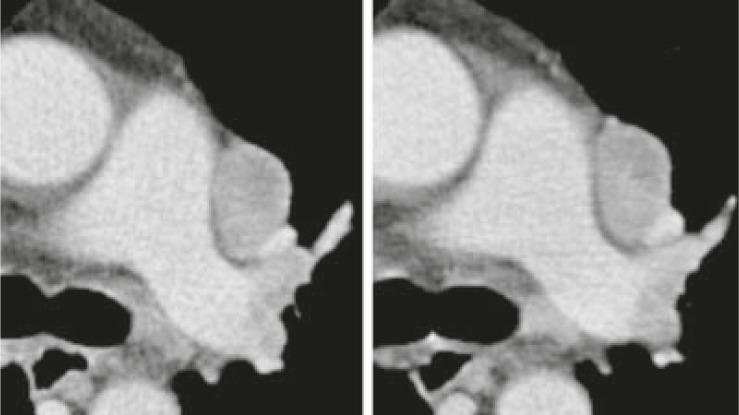

Twenty oncologic patients were included to the study with CT examinations from thorax to pelvis performed at a 64 slices CT scanner. Four readers defined and measured the size of target lesions independently at baseline and follow-up with PACS (Picture Archiving and Communication System) and LMS (Lesion Management Solutions, Median technologies, Valbonne Sophia Antipolis, France), according to the RECIST 1.1 criteria. Variability in measurements using PACS or LMS software was established with the Bland and Altman approach. The inter- and intra-observer variabilities were calculated for identical lesions and the overall response per case was determined. In addition, time required for evaluation and reporting in each case was recorded.

For single lesions, the median intra-observer variability ranged from 4.9-9.6% (mean 5.9%) and the median inter-observer variability from 4.3-11.4% (mean 7.1%), respecting different evaluation time points, image systems and observers. Nevertheless, the variability in change of Δ sum longest diameter (LD), mandatory for classification of the overall response, was 24%. The overall response evaluation assessed by a single respectively different observer was discrepant in 6.3% respectively 12% of the cases compared with the mean results of multiple observers. The mean case evaluation time was 286s vs. 228s at baseline and 267s vs. 196s at follow-up for PACS and LMS, respectively.

本研究纳入 20 名肿瘤患者,在 64 层 CT 扫描仪上进行胸部至骨盆的 CT 检查。四位读者使用 PACS(影像归档和通信系统)和 LMS(病灶管理解决方案,中位数技术,法国瓦尔布勒索菲亚安提波利斯)独立定义和测量基线和随访时的目标病变大小,根据 RECIST 1.1 标准。使用 Bland 和 Altman 方法确定 PACS 或 LMS 软件测量中的变异性。计算相同病变的观察者内和观察者间变异性,并确定每个病例的总体反应。此外,还记录了每个病例评估和报告所需的时间。

对于单个病变,观察者内变异性中位数范围为 4.9-9.6%(平均 5.9%),观察者间变异性中位数范围为 4.3-11.4%(平均 7.1%),考虑到不同的评估时间点、影像系统和观察者。然而,对于分类总体反应必需的Δ总和最长直径(LD)的变化的变异性为 24%。与多位观察者的平均结果相比,单个观察者或不同观察者评估的总体反应评估结果不一致的病例分别占 6.3%和 12%。使用 PACS 和 LMS 的平均病例评估时间分别为 286s 与 228s(基线)和 267s 与 196s(随访)。